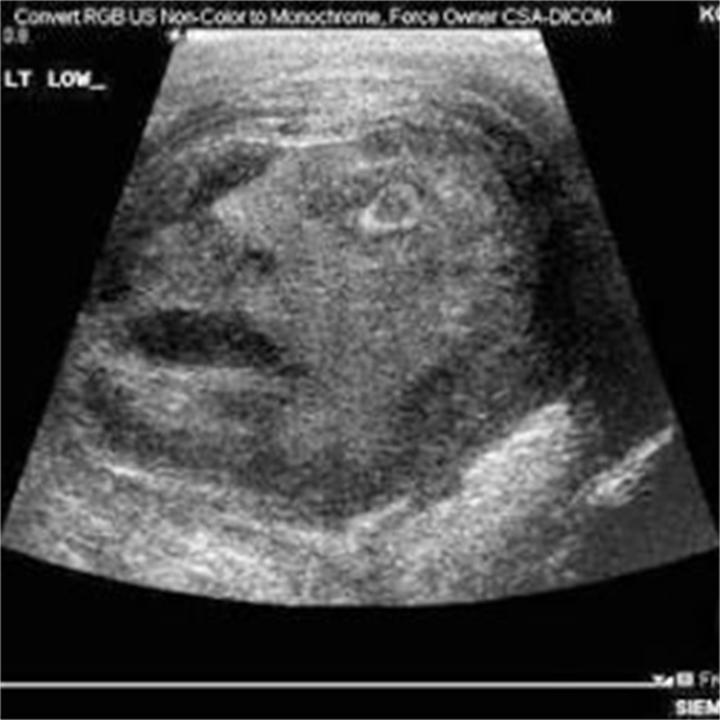

Apparently a man had an ultrasound done because of a mass in his testicle. The CT scan comes from Dr. G. Roberts of the School of Medicine at Queens University, Kingston.

Obviously it’s pareidolia but so very freaky none the less. Here’s the photo along with a short description from the source:

The picture on this post claims to be an ultrasound image, again of a man who had a ‘mass in his testicle’. As you can see it shows what appears to be a face of a man who looks to be in pain – and in the circumstances, why wouldn’t this testicle be in pain!

There is a quote said to have been made by Dr G Roberts of the School of Medicine at Queens University, Kingston: “It looked like a man screaming in pain, which I thought was hilarious considering the clinical picture of the poor guy.”